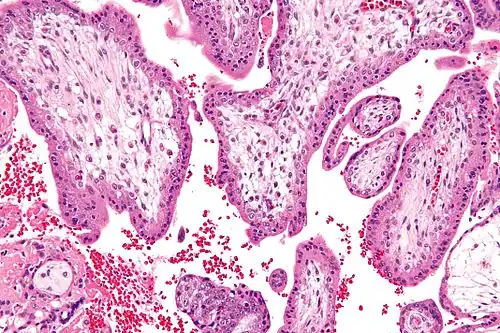

Micrograph showing chorionic villi—the tissue that is collected in CVS. H&E stain.

Chorionic villus sampling (CVS), sometimes called "chorionic villous sampling" (as "villous" is the adjectival form of the word "villus"),[1] is a form of prenatal diagnosis done to determine chromosomal or genetic disorders in the fetus. It entails sampling of the chorionic villus (placental tissue) and testing it for chromosomal abnormalities, usually with FISH or PCR. CVS usually takes place at 10–12 weeks' gestation, earlier than amniocentesis or percutaneous umbilical cord blood sampling. It is the preferred technique before 15 weeks.[2]